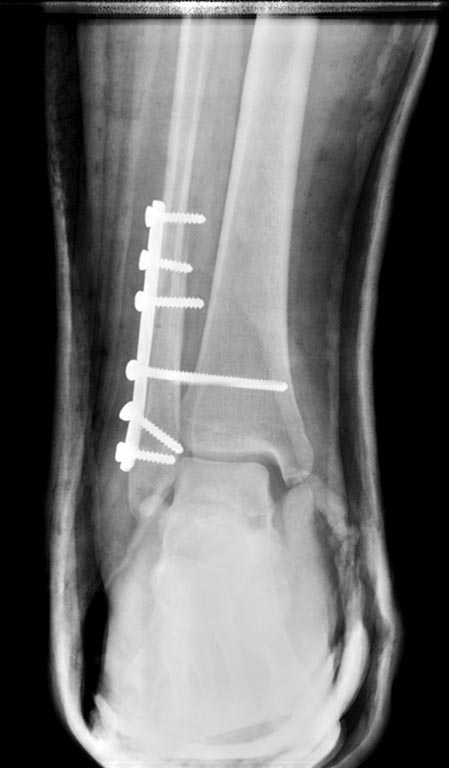

Перелом наружной лодыжки с разрывом ДМС и дельтовидной связки и

подвывихом стопы. Пациенту 17 лет, полного телосложения. На контроле

сохраняется небольшой подвывих стопы. Шов дельтовидной связки не

выполнялся. Так оставлять или реостеосинтез? Интересует дальнейшая

тактика. Смущает молодой возраст пациента...